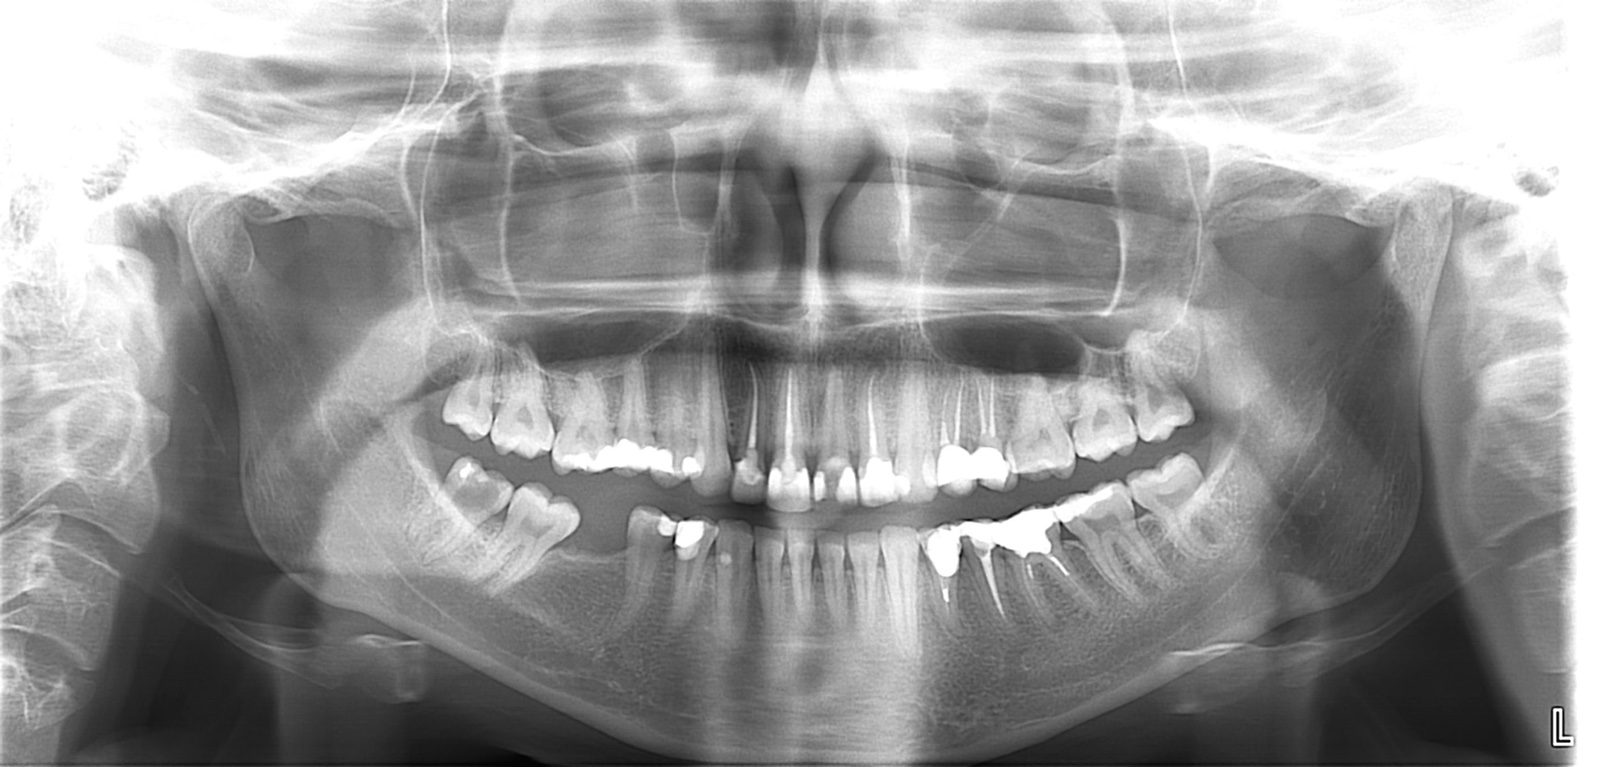

je tu nejaka ochotna osoba, ktora by mi popisala rtg snimok ? Hlavbe by ma zaujimalo, kolko mam celkovo mrtvych zubov a kolko je nespravne urobenych endodencii, resp ci su tam nejake zapaly, loziska, nakolko mi mrtve zuby umrtvovala zubarka pred rokmi, bez mikroskopu….

Vidím tam 8 endodoncii a takto nezvacsene vidím zle urobené 3-4. Keď dáš snímku do komentu, lepšie to uvidím

To ako je zaplnený kanalik nemusí vôbec súvisieť s tým, či v ňom infekcia zostala. Chemické vyčistenie kanálikov - správny výplach je oveľa dôležitejšie. Z opg snímku by som určite žiadny záver nerobila. Určite sú nutne malé intraoralne snímky. Ak na malých rtg nebude zápal a nie sú žiadne ťažkosti, určite by som ich nechytila. Jedine, ak by sa plánovala nejaká protetika. Ale podozrivo vyzerajú za mňa zuby 22, 36,34.

@astrid99 všetky tri sú zlé ale ak nerobia problém nechať tak. Ta dvojka je dobre zaplnená v pravo hore ale ma takú gulicku nad koreňom, to treba s rtg skontrolovať ci sa zmenšuje alebo nie. Ak nie skôr ako prerobiť by som resekciu spravila, tam sa odstráni špička koreňa s tou cestou, zub ostane, ale aj ta ľavá dvojka ma okolo koreňa taky tieň čiže ten tiež sledovať. Co sa týka tej osmičky to je také sporné. Je to zub ktorý sa používa, nie je len do počtu lebo je aj hore osmička a keď by sa dal von dole, tak časom aj horny lebo ten by klesal dole. Na tej strane už zub chyba a ta osmička sa používa na zuvanie, čiže sa ta sedmička nepretazuje nadmerným používaním. Tam to miesto ako bola šestka vyzerá dobre, že je tam dosť kosti na implantát. To samozrejme ešte musí implantolog zhodnotiť ale podla tohto by sa mal dat spraviť. To sú výhody aby osmička ostala. Co je ale nevýhoda oni sú u každého inak, môže mať kanaliky 2 alebo kľudne aj 5, môžu sa spájať v nejakom bode a nemusia. Pri nich je najväčšie riziko ze to môže zlyhať, nemusí sa podariť dobra endodoncia ani pod mikroskopom. Ale ja by som skúsila. A este prečo píšem o implantate. Keďže tam chyba zub, môže horny trochu klesnúť do medzery, nie hneď ale časom, keď sa kosť nezaťažuje mizne, čiže časom by sa nemusel dat implantát, čím ďalej dozadu, tým je väčšie riziko ze sa nedá spraviť implantát lebo tam zasahuje nerv. Keď je vyplnená medzera, sila pri hryzeni sa rozloží na viac zubov, menej sa ohrozujú okolité zuby. Hygiena je ako pri vlastných zuboch, cena za implantát je ako za mostík. Ak by sa robil mostík, musia sa obrusit susedné zuby, a oni sú relatívne zdrave, nejaké male výplne a berie sa z tých zubov dosť pri bruseni, ak by sa niečo stalo s niektorým tým zubom pod korunkou lebo aj ten sa vie pokaziť musí ísť dole celý mostík, je to zložitejšie na hygienu. Ak by aj bol náhodou implantát a sa susedné zuby pokazia je ľahšie ich opraviť, lebo zubar si vie aj ru korunku dat dole a spraviť kaz na vedľajšom zube a nemusí veľa vŕtať. Ak by bol mostík a vytiahne sa ďalší zub, musí sa robiť nový mostík, zväčša sa implantatmi nahrádza len do šestku, málokedy sedmička. Ale da sa spraviť taká menšia ze by sa len prerobila koru ka implantatu a mala na sebe taky zub ako je päťka pred ňou, čiže polovičný lebo to udrží implantát. Čiže zase sa nemusí nič zbytočne brúsit.